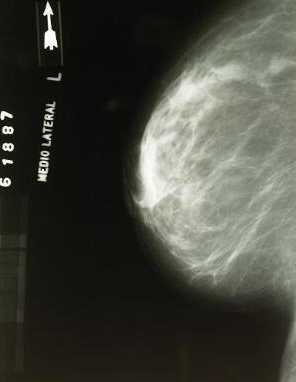

我們所經過的安全門叫X射線安檢儀,這個設備技術是采用X射線掃描技術,它內部裝有高靈敏度探測器,對被檢測物體逐層掃描,最后通過成像處理技術對人體物品進行行透光檢查,能夠及時展現內部信息,可以準確查看是否攜帶違禁物品!

所以當咱們女性過安檢時,不管穿脫后都可以掃描的到,而且對于女性就沒有隱私可言,隆胸的硅膠在X光下也是可以看得清清楚楚的,這項技術也取代了傳統人工檢查的麻煩,男性給女性檢查時的尷尬。

這種探測儀可以發現看到透視全身,沒有什么東西能夠藏住。像有一些女性的隆胸硅膠、內增高,甚至身上哪個地方有金屬環,這些都能被看到。所以現在很多女性不愿意過安檢,首先覺得就很尷尬。另外有些人這個太沒有隱私了。但是這個跟我們的日常安全來比,還是日常安全重要得多。